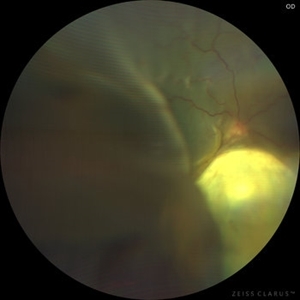

Total Rhegmatogenous retinal detachment with opened posterior margin of lattice degeneration

Jul 18 2023 by Harsh Vardhan Singh, MS

78-year-old man with history of defective following cataract surgery showed total retinal detachment on examination

Photographer: Harsh Vardhan Singh, AIIMS, Guwahati

Imaging device: Zeiss Clarus 700

Condition/keywords: chronic retinal detachment, peripheral lattice degeneration, rrd